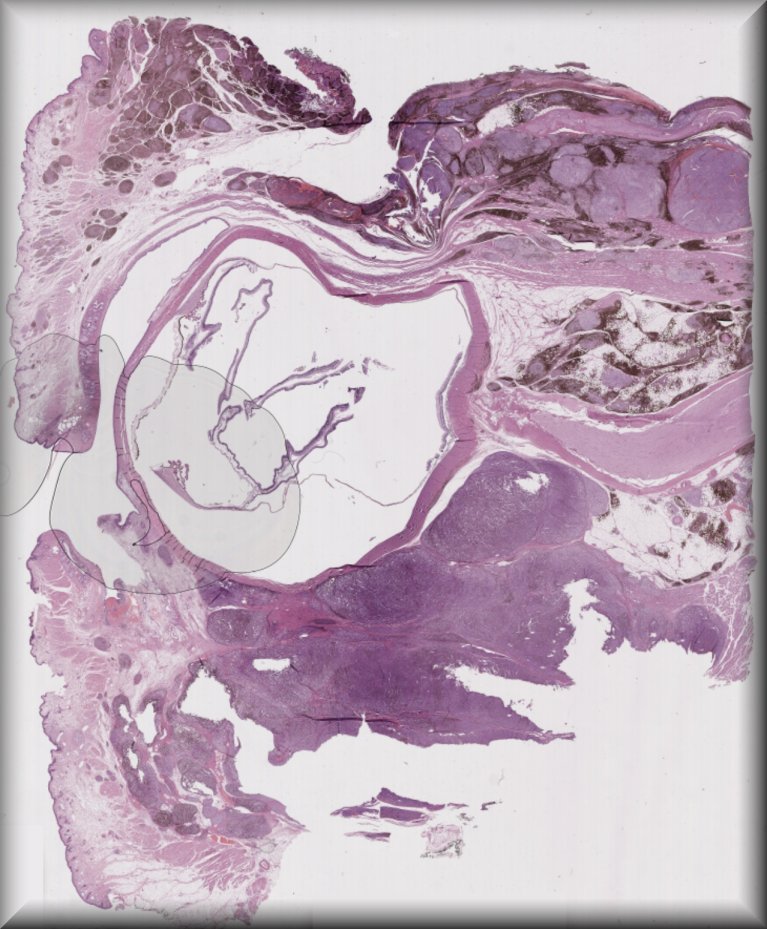

Susan Kennedy: Exenteration specimen of a 70-year-old female who underwent multiple (14) surgeries for conjunctival melanoma over a period of two years. |